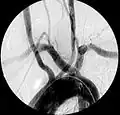

Aberrant subclavian artery at axial CT-scan. (1) trachea, (2) esophagus, (3) aberrant subclavian artery. -

Aberrant right subclavian artery at angiography.